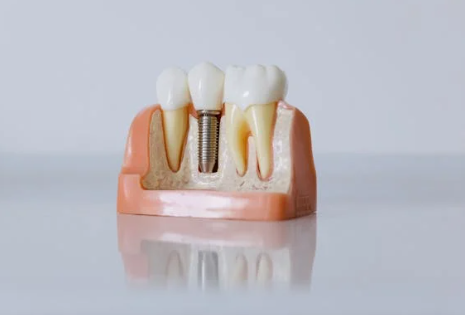

임플란트란 무엇인가요?

임플란트란 치아가 빠졌을 때 인공치근(임플란트)을 잇몸 뼈에 식립해 자연치아처럼 기능하게 만드는 치료입니다.

자연치에 가까운 기능과 외관을 제공하기 때문에 많은 분들이 임플란트를 선택하고 있습니다.